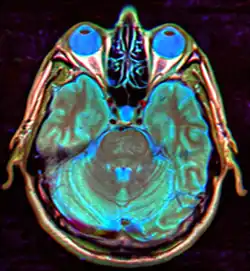

A síndrome da sela vazia é um conjunto de sinais e sintomas, que expressam o aumento considerável da sela túrcica, sendo uma deficiência do diafragma da sela. Nesta síndrome, a sela túrcica está preenchida com líquido cefalorraquidiano, o que leva a compressão da hipófise. É mais comum em mulheres e pode ser detectada através de exames radiológicos. Seu principal sintoma é a cefaleia.[1]